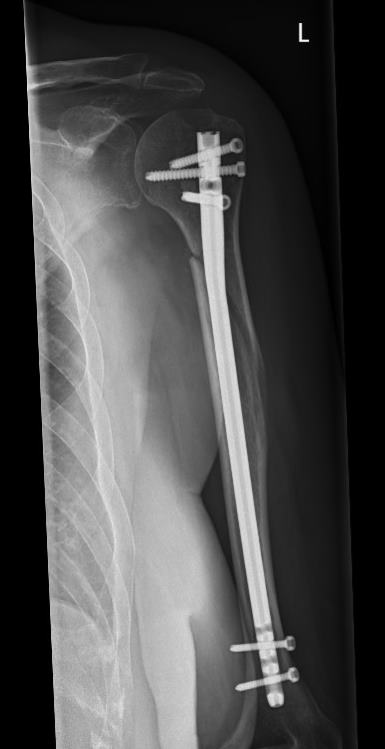

Einen weiteren Schwerpunkt in der Traumabehandlung stellt die Versorgung von Schulterbrüchen dar.

Während bei jüngeren Patienten die Rekonstruktion von Knochen und Gelenken im Vordergrund steht, führt bei älteren Patienten häufig der Gelenkersatz zur schnelleren Wiederherstellung der Beweglichkeit.

Hierfür kann die umfangreiche Erfahrung der orthopädischen Klinik in der Schulterendoprothetik angewandt werden. Dazu werden die Art der Endoprothese und die Einsatzmöglichkeit individuell geplant und umgesetzt.